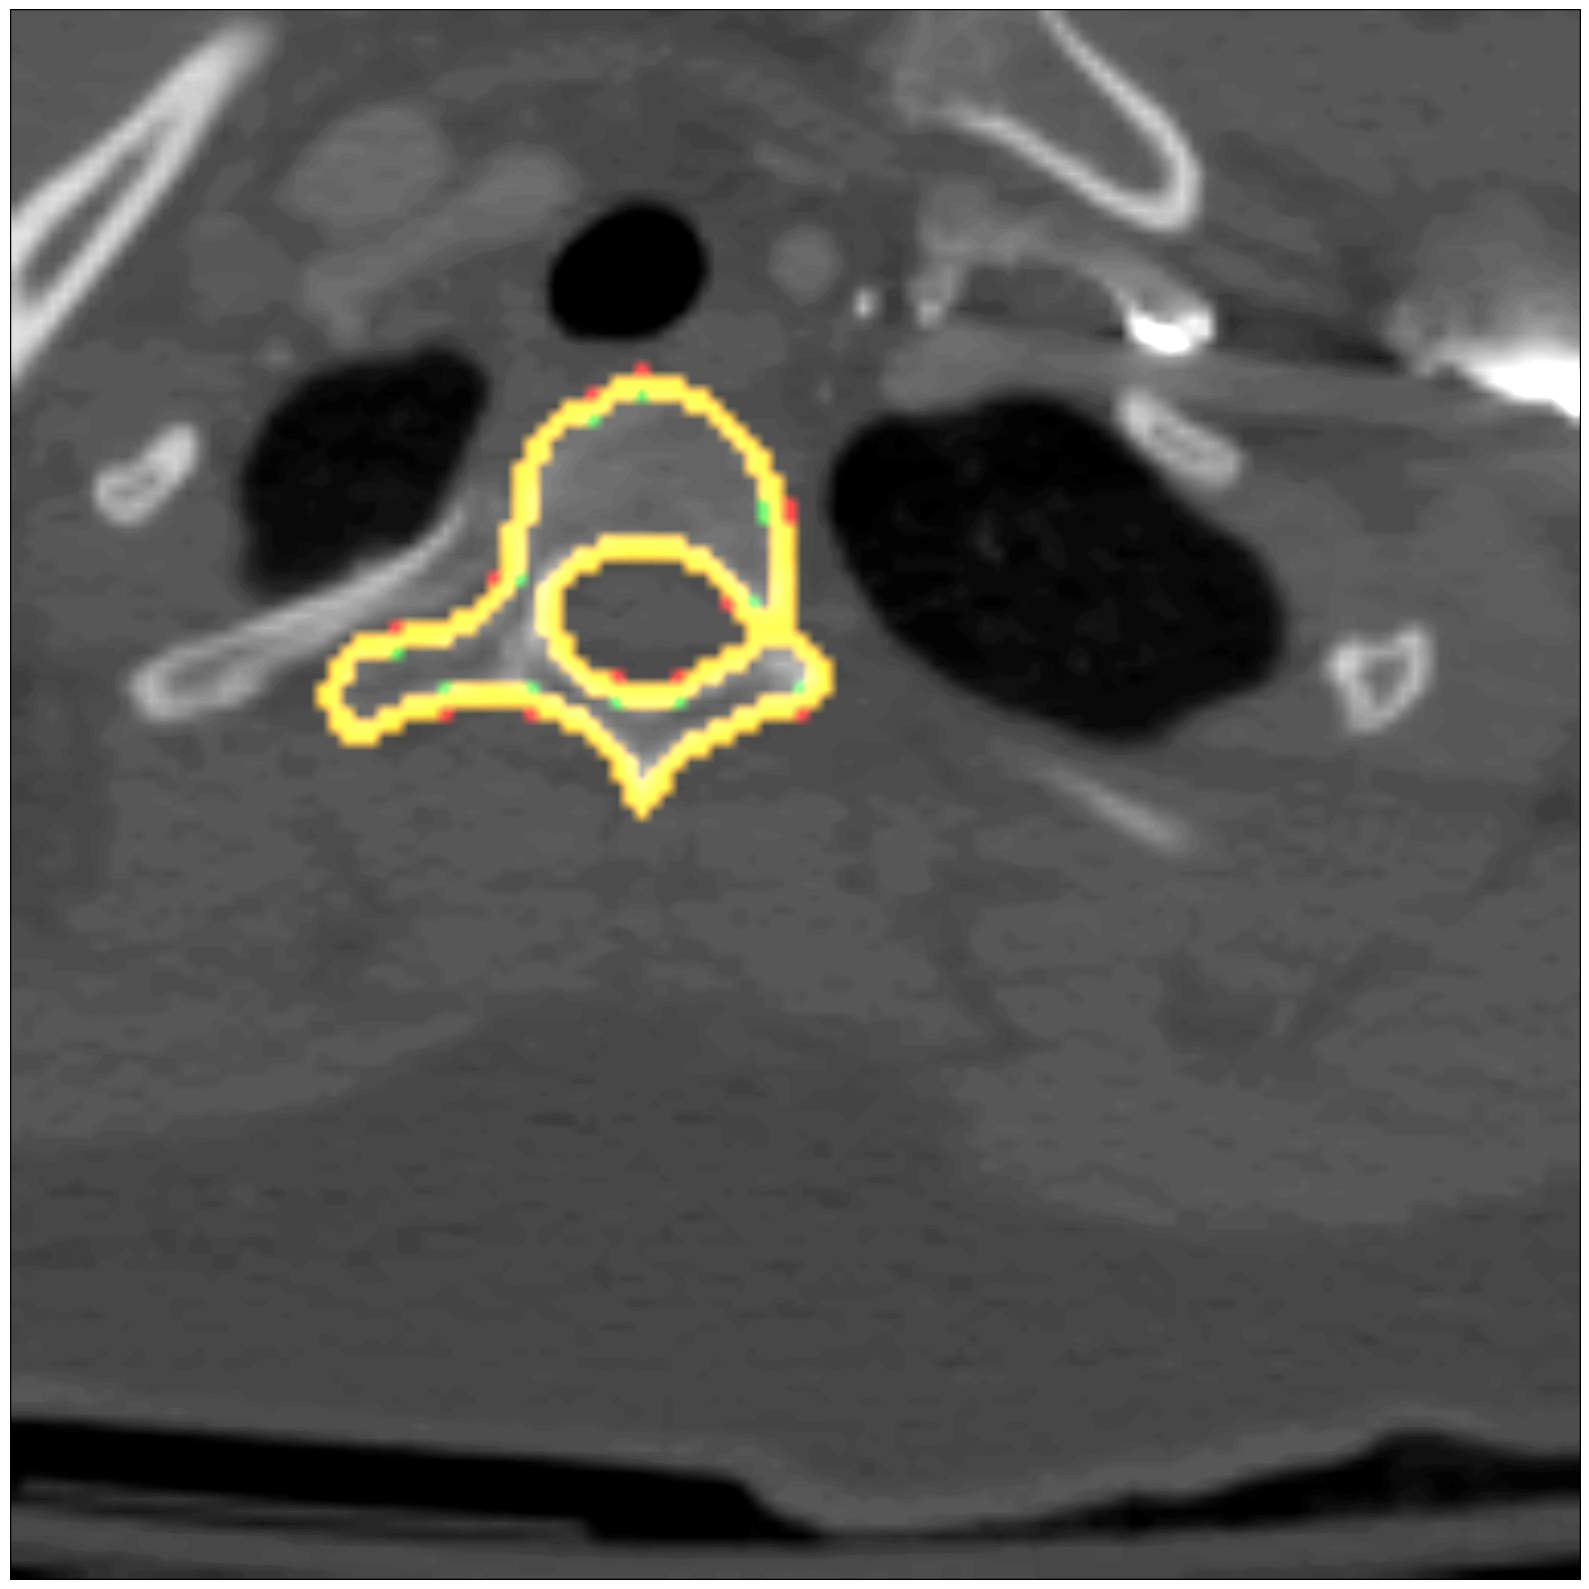

Some segmentation results at different vertebrae (top) and liver (bottom) areas are depicted in Fig. 2. The red contour corresponds to the outline of the prediction, green to the ground-truth and yellow to the overlap of the outlines.